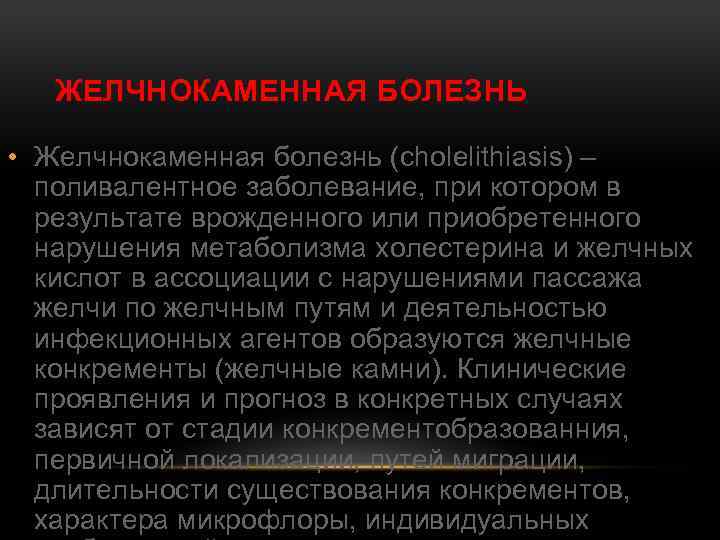

ЖЕЛЧНОКАМЕННАЯ БОЛЕЗНЬ • Желчнокаменная болезнь (cholelithiasis) – поливалентное заболевание, при котором в результате врожденного или приобретенного нарушения метаболизма холестерина и желчных кислот в ассоциации с нарушениями пассажа желчи по желчным путям и деятельностью инфекционных агентов образуются желчные конкременты (желчные камни). Клинические проявления и прогноз в конкретных случаях зависят от стадии конкрементобразованния, первичной локализации, путей миграции, длительности существования конкрементов, характера микрофлоры, индивидуальных

ЖЕЛЧНОКАМЕННАЯ БОЛЕЗНЬ • Желчнокаменная болезнь (cholelithiasis) – поливалентное заболевание, при котором в результате врожденного или приобретенного нарушения метаболизма холестерина и желчных кислот в ассоциации с нарушениями пассажа желчи по желчным путям и деятельностью инфекционных агентов образуются желчные конкременты (желчные камни). Клинические проявления и прогноз в конкретных случаях зависят от стадии конкрементобразованния, первичной локализации, путей миграции, длительности существования конкрементов, характера микрофлоры, индивидуальных